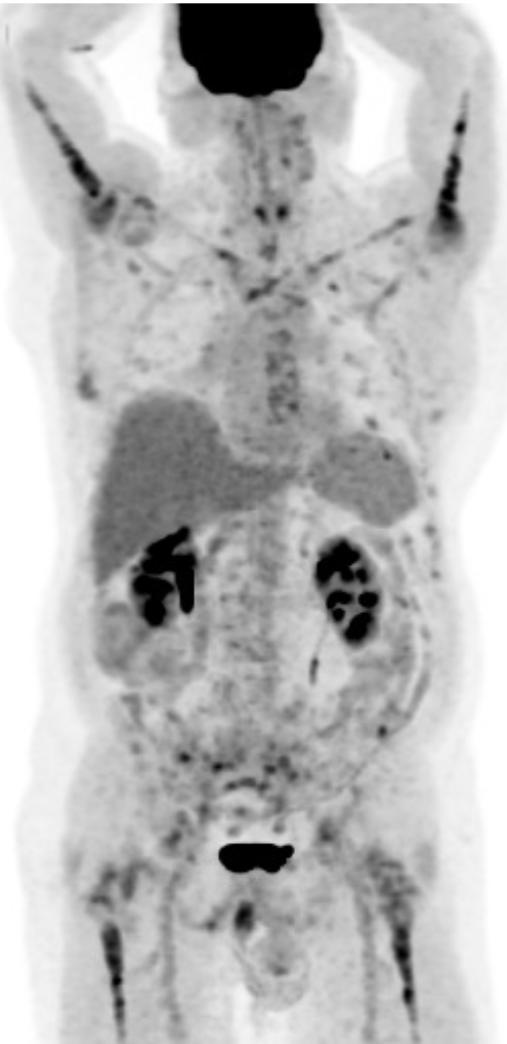

Aux figures 3 et 4, nous pouvons voir le même patient en TEP Ga68-PSMA et TEP F18-FDG avant le début des traitements. Sur la figure 5, nous avons le même patient environ 3 mois après la fin de ses 6 cycles de traitements.